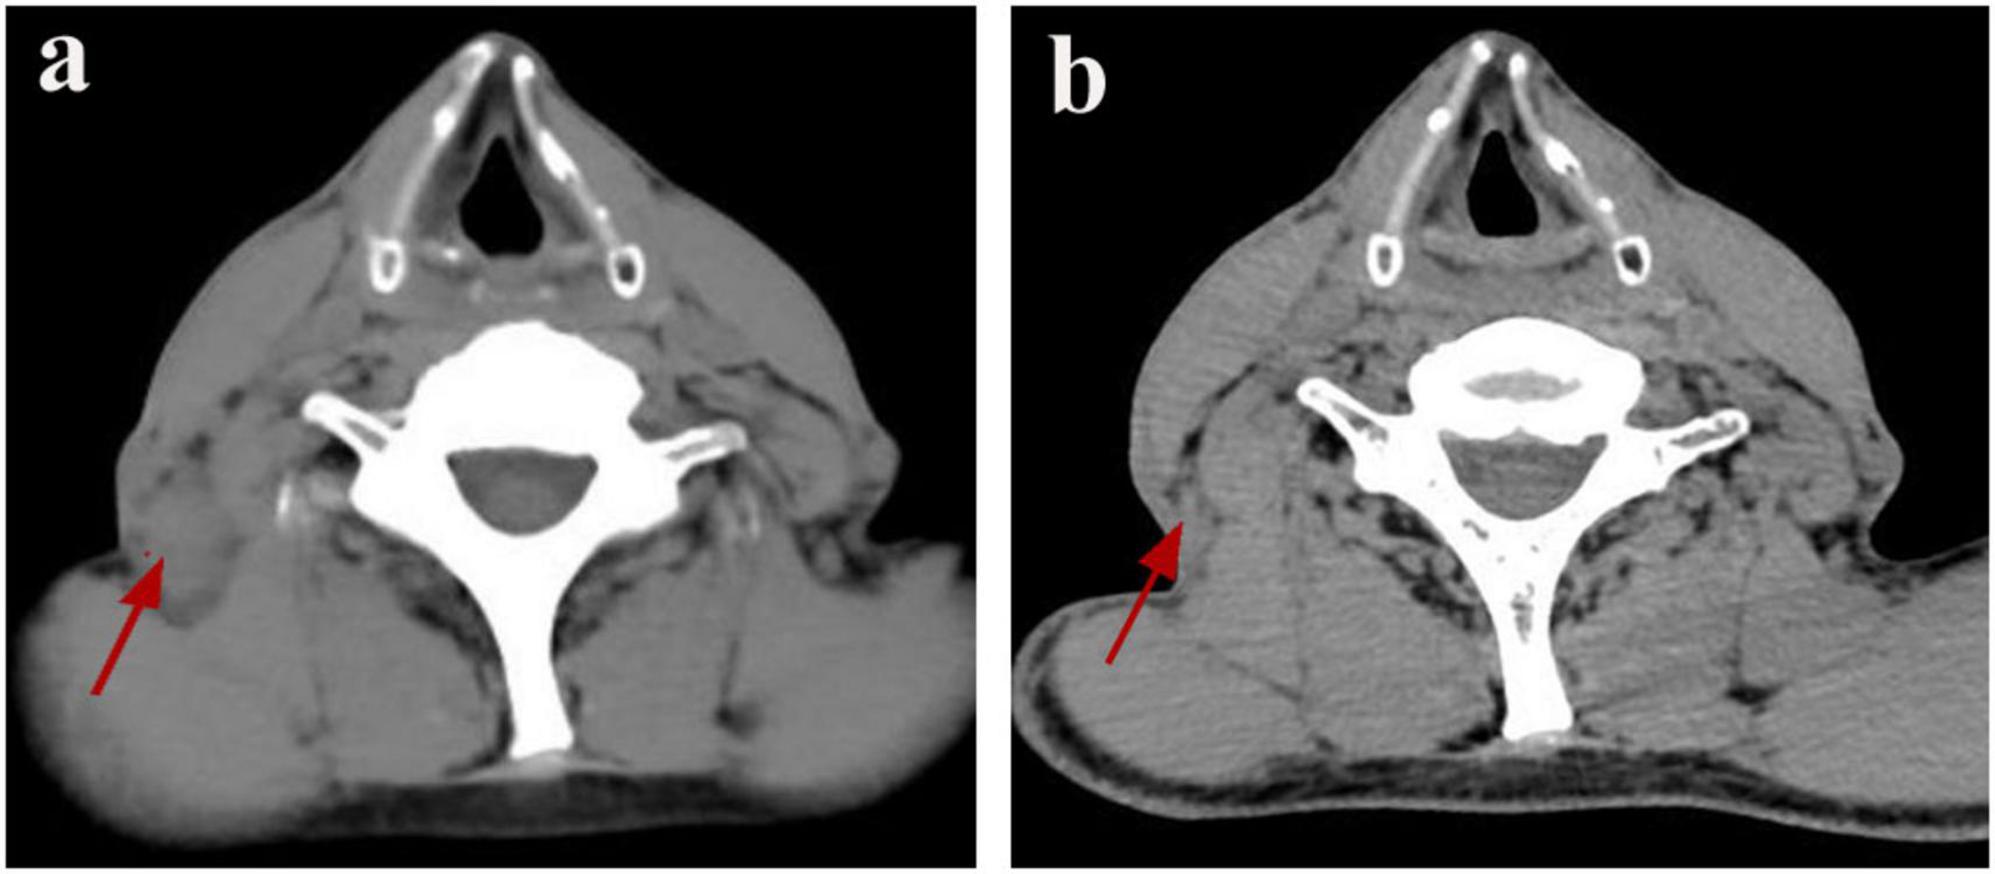

FIGURE 1

Resolution of CSD-associated lymphadenopathy on serial cervical CT. (a) Pre-treatment CT scan (January 8, 2025) demonstrates an enlarged right posterior cervical lymph node (red arrow). (b) Follow-up CT scan (March 26, 2025) shows the enlarged lymph node in the right posterior cervical space has disappeared (red arrow).

A bronchoscopy performed at our facility revealed no irregularities; however, the bronchoalveolar lavage fluid tested positive for TB-DNA, suggesting the presence of pulmonary tuberculosis. During a detailed history review, the patient disclosed having two cats for the past 2 years. Although there was no clear record of cat scratches, the possibility of CSD was considered due to negative results from PAS, silver methenamine, and acid-fast staining, along with the patient’s exposure to cats. Metagenomic pathogen detection workflow (MetaPath™)–a probe-enriched metagenomic next-generation sequencing (mNGS) method optimized for low-biomass specimens–successfully detected B. henselae sequences, rather than MTB, in formalin-fixed paraffin-embedded (FFPE) histopathological sections of a cervical lymph node specimen obtained externally. MetaPath™ technology of the cervical lymph node tissue detected sequences specific to B. henselae, identifying 82 sequences at a relative abundance of 7.19%, thereby confirming a diagnosis of CSD. The patient presented with lymphadenopathy, and pathological findings revealed granulomatous inflammation. The differential diagnoses include infectious etiologies such as tuberculosis, non-tuberculous mycobacterial infection, and fungal infections, as well as non-infectious conditions such as sarcoidosis and lymphoma. Based on comprehensive clinical, laboratory, radiological, pathological, etiological, and molecular evaluations, the patient final diagnoses included: (1) cervical lymphadenitis related to CSD; (2) pulmonary tuberculosis; and (3) emphysema with bullae. The patient commenced anti-tuberculosis therapy on January 18, 2025, following a regimen consisting of Isoniazid, Rifampicin, Pyrazinamide, and Ethambutol for 2 months, followed by a 4-month continuation of Isoniazid and Rifampicin. Subsequently, upon the detection of Bartonella species via MetaPath™ testing on January 23, 2025, ciprofloxacin was added for a duration of 4 weeks to address cat-scratch disease, targeting anti-Bartonella therapy. A follow-up CT scan of the chest and neck conducted on March 26 indicated partial resolution of the lesion in the left upper lung (Figure 1b) and nearly complete reduction of the enlarged lymph nodes in the right posterior cervical area (Figure 2b).